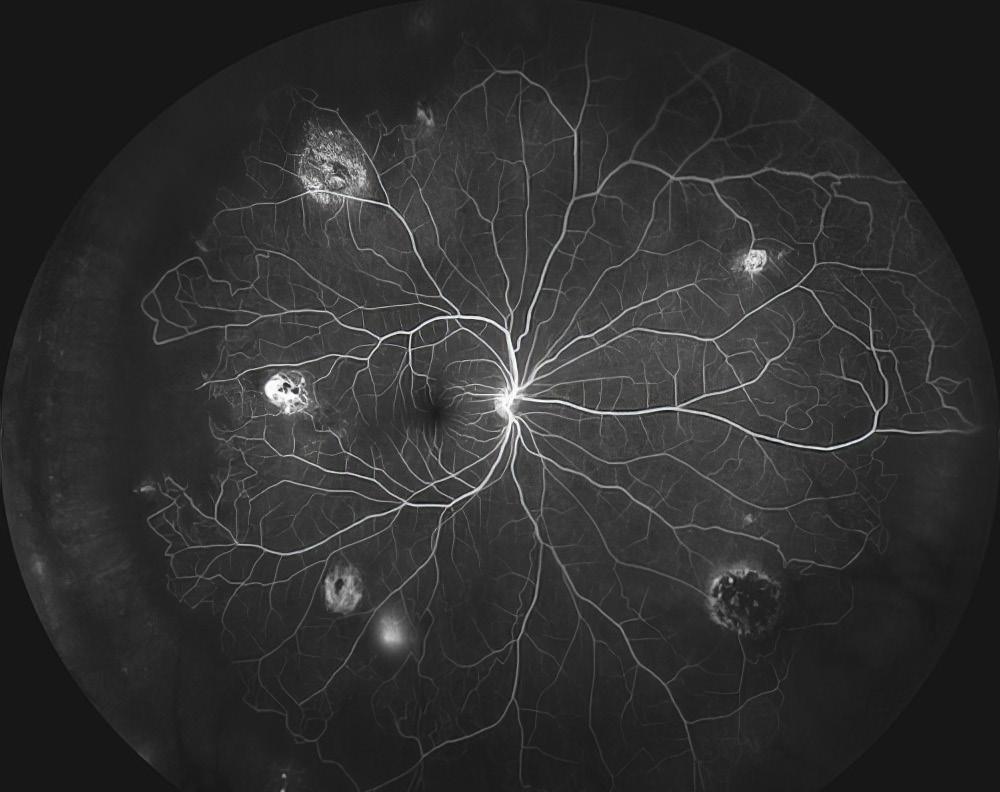

OPS Exhibit at AAO, First Place in the Video Category: Giant Cell Arteritis, Second Place in the Fluorescein Angiography Category: Unknown Third Place in the Fluorescein Angiography Category: Sickle Cell Retinopathy, Honorable Mention in Gonio Photography: Unknown, Honorable Mention in Ultra-Widefield Imaging: Choroidal Detachment with Retinal Tear.

Select Photography Award Images, clockwise from top left: Posterior Uveitis by Christopher Keth, BA, CRA; Santos Klimt by Veronica Jones, BA; Sickle Cell Retinopathy by Christiaan Lopez-Miro; Choroidal Detachment with Retinal Tear by Christiaan Lopez-Miro.